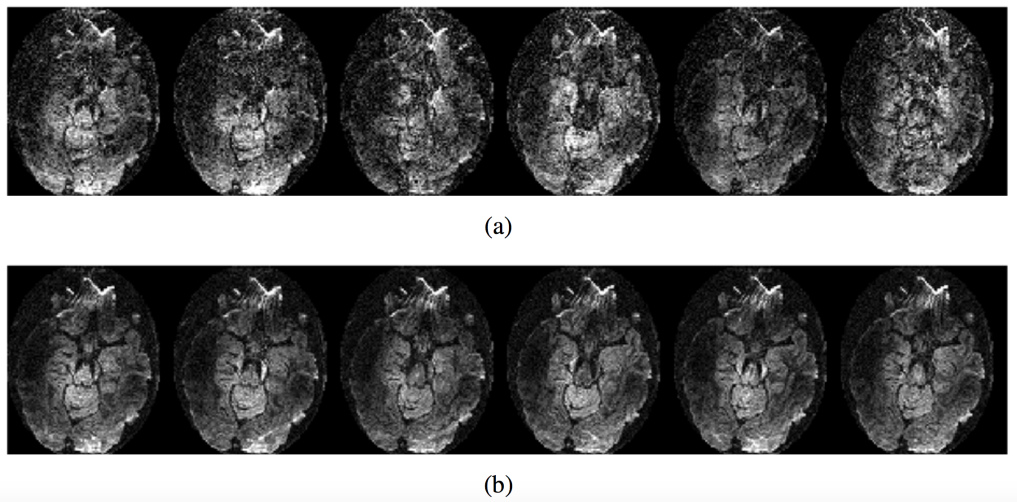

Figure 4 demonstrates the effect of TE on image quality of the DWIs collected at 7 Tesla. Because of the short T2 relaxation times at higher field strengths, shorter TEs becomes extremely desirable for studies at higher field strengths. 4-shot or higher number of shots provide good SNR and provide a significant reduction in the TE. As a result, susceptibility related artifacts are also minimized. The MUSE method has been shown to be effective in unaliasing the motion-induced ghosting artifacts for a 4-shot DWI acquisition when good phase estimates are available (26). For this reason, we implemented the MUSE method and we compare the proposed reconstruction with this method. For the purpose of comparing with the proposed regularized reconstruction, which included a smoothness constraint, the MUSE algorithm also included an iterative reconstruction using the TV constraint.

Fig 4: Effect of long echo times at 7T demonstrated on non-diffusion weighted images collected using different number of shots for a 128 x 128 acquisition matrix. Due to the shortened T2 relaxation times, high signal drop-out are observed in many regions of the single and two-shot acquisitions as pointed out by the circles. The SNR computed from the ROIs as a function of the number of shots are shown in the last column. No parallel imaging acceleration was employed in these acquisitions. However, with single-shot imaging, it is common to employ parallel imaging acceleration of at least 2, in which case, the TE becomes comparable to the 2-shot case in column two.